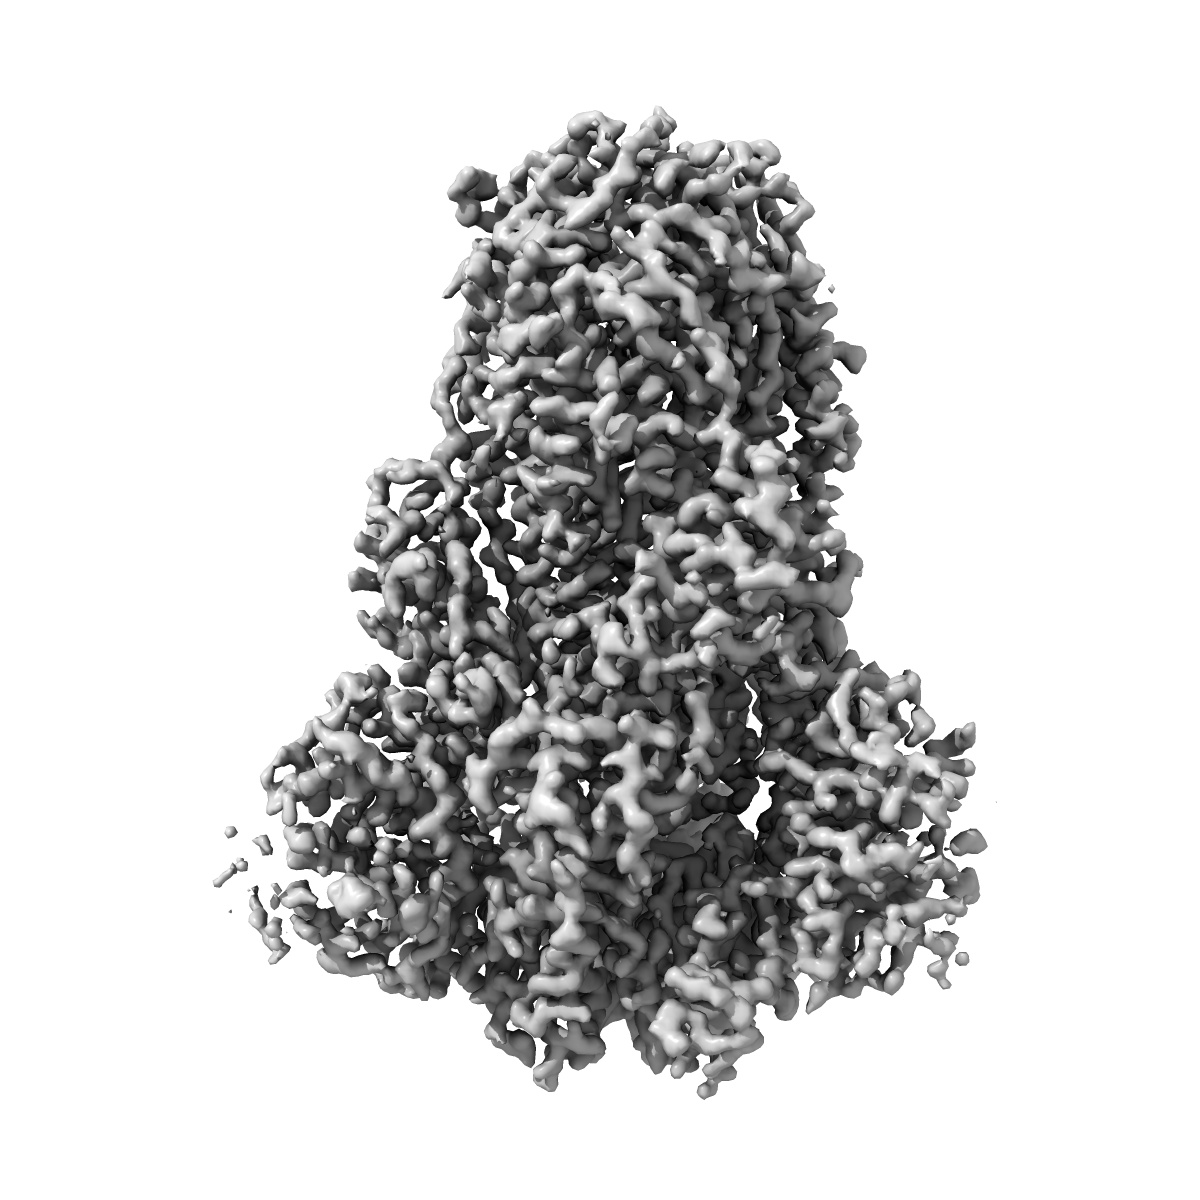

EMD-26798

SARS-CoV-2 spike protein closed conformation

Single-particle3.56 Å

Deposition: 28/04/2022Map released: 15/02/2023

Sample: Spike glycoprotein

Direct Cryo-ET observation of platelet deformation induced by SARS-CoV-2 spike protein.

(2023) Nat Commun , 14 , 620 - 620